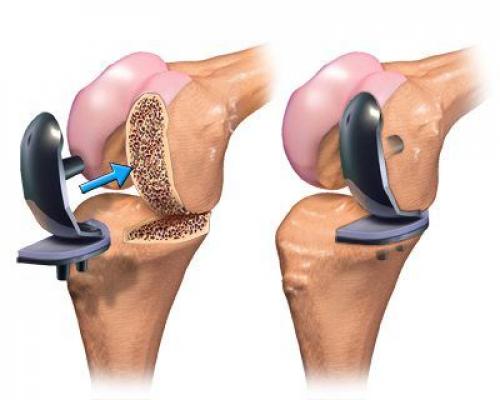

Фотографии и примеры протезирования коленного сустава